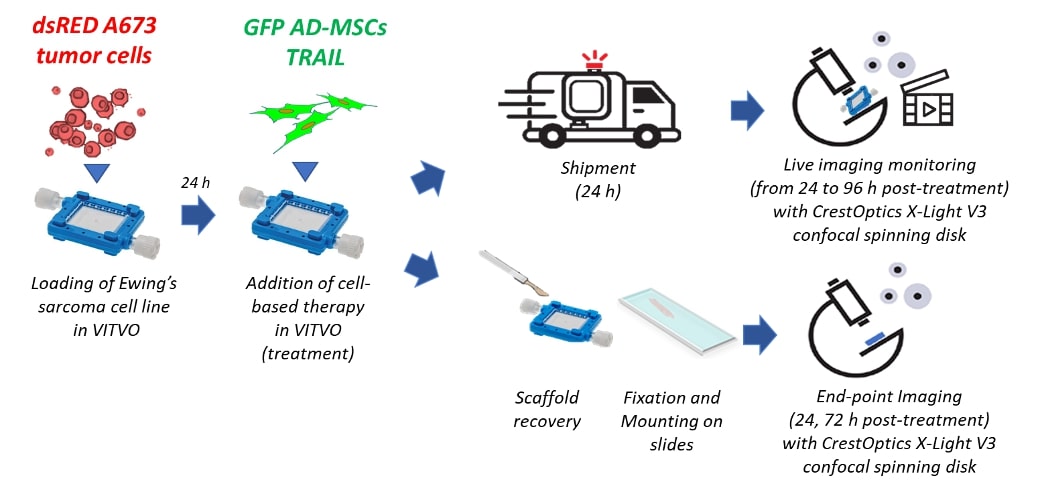

VITVO® is an in vitro innovative pre-clinical testing tool, which is presented under the form of a ready-to-use device. This device is composed by a fiber-based matrix for 3D cell colonization, to mimic tissue complexity [2]. VITVO can simultaneously host target and effector cells, allowing both to evaluate the antitumor action and to identify the effective dose. In this study gene-modified adipose derived mesenchymal stromal/stem cells expressing the anticancer molecule TRAIL (AD-MSC TRAIL) [3] have been challenged for their capacity to induce apoptosis in Ewing’s sarcoma (A673 tumor cell line).

In order to directly monitor the anti-cancer therapy effect of AD-MSCs TRAIL on A673 Ewing’s sarcoma cells at single cell level, we performed time-lapse experiment with CrestOptics X-Light V3 confocal spinning disk, starting from 24 hours (h) post-treatment and monitoring till 96 h post-treatment, following 3 different fields inside the same VITVO environment. Moreover, end-point imaging was performed on fixed samples by using CrestOptics X-Light V3 confocal spinning disk as confirmation.

Figure 1. Experimental workflow.